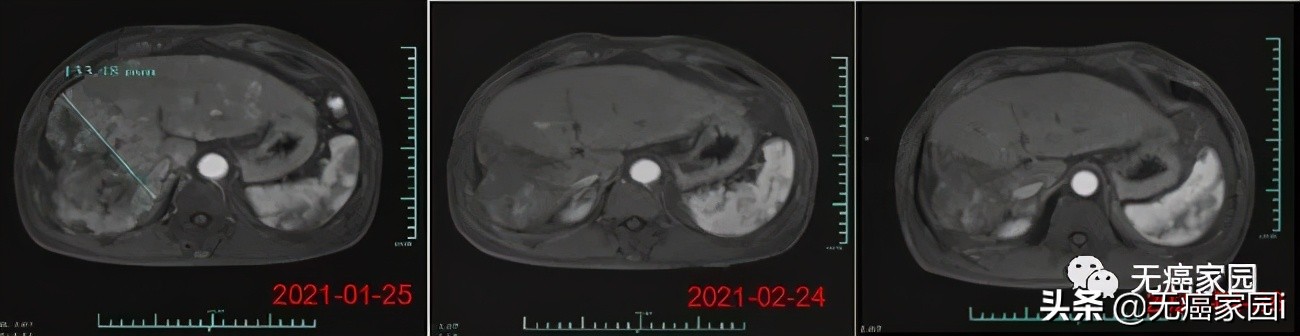

在输注CAR-T细胞后的第28天, 受试者MRI结果显示最大肿瘤直径从最初的 133毫米减少至9毫米,缩小超过93%。目前,该受试者正在接受CAR-T细胞输注后第3个月的评估,MRI扫描显示此肿瘤几乎消失。 此外,甲胎蛋白(AFP,原发性肝癌的特定肿瘤标志物)水平从基线值 >80,000/ng/ml 下降到第1个月的1148.9ng/ml,并在第3个月下降到746.7ng/ml输注(正常范围<40ng/ml),证明 Ori-CAR-001 在晚期肝癌患者中具有显著的初步疗效。

受试者012的MRI结果示意图